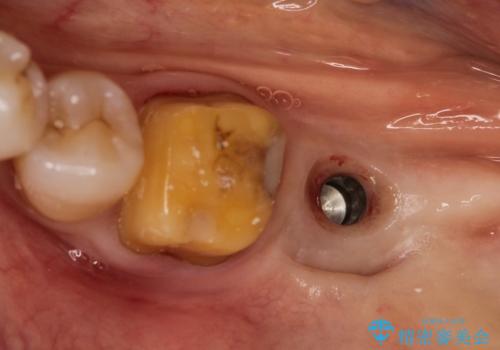

- 左下の1番後方の歯が欠損しており、インプラントにて咬合回復する計画としました。

レントゲン・CT撮影により骨の高さがあまりないことがわかり、ショートインプラントを選択しました。

また、清掃性を確保するために歯肉の移植も行うこととしました。